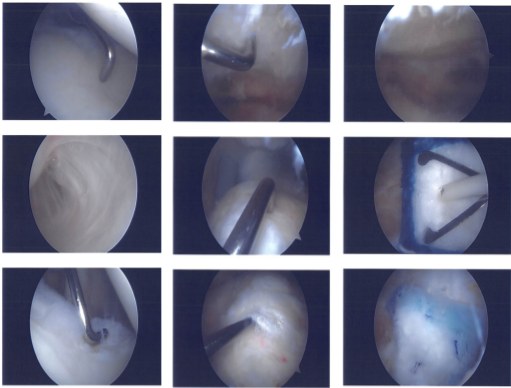

Case Study: Shoulder Arthroscopy: Rotator Cuff Repair with the Use of Medical Rotation Implant and Acromioplasty in a 22 year-old male

An anterior portal was created for posterior entrance at the soft point. The arthroscope was implanted. The spinal needle was used to create an anterior and superior entrance hole. An examination of the shoulder joint revealed fraying of the anterior and posterior glenoid labrums.

The biceps were discovered to be completely intact. The rotator interval was fraying. Shaving revealed fraying of the labrum as well as the rotator interval. The cartilage was found to be undamaged.

The rotator cuff’s intra articular tear was nonexistent. The subacromial space was used to implant the arthroscope. The front of the probe was inserted. from the anterosuperior portal was inserted. There was a subacromial bursectomy.

Over the acromion’s underside, there were indications of impingement. Additionally, an infraspinatus partial tear was discovered. There was a debridement of the tear. The choice was made to use a medical rotation implant to heal the tear.

Additionally, the acromial spur was removed using a thermal wand and a bur. An acromioplasty was done. The AC joint was discovered to be in excellent form with no impingement.

Using a tiny rotation implant that was connected to the rotator cuff tendon using numerous screws, the decision was made not to repair a partial tear of the infraspinatus. Final images were captured and stored. It was irrigated and drained on the knee.

Clinical images